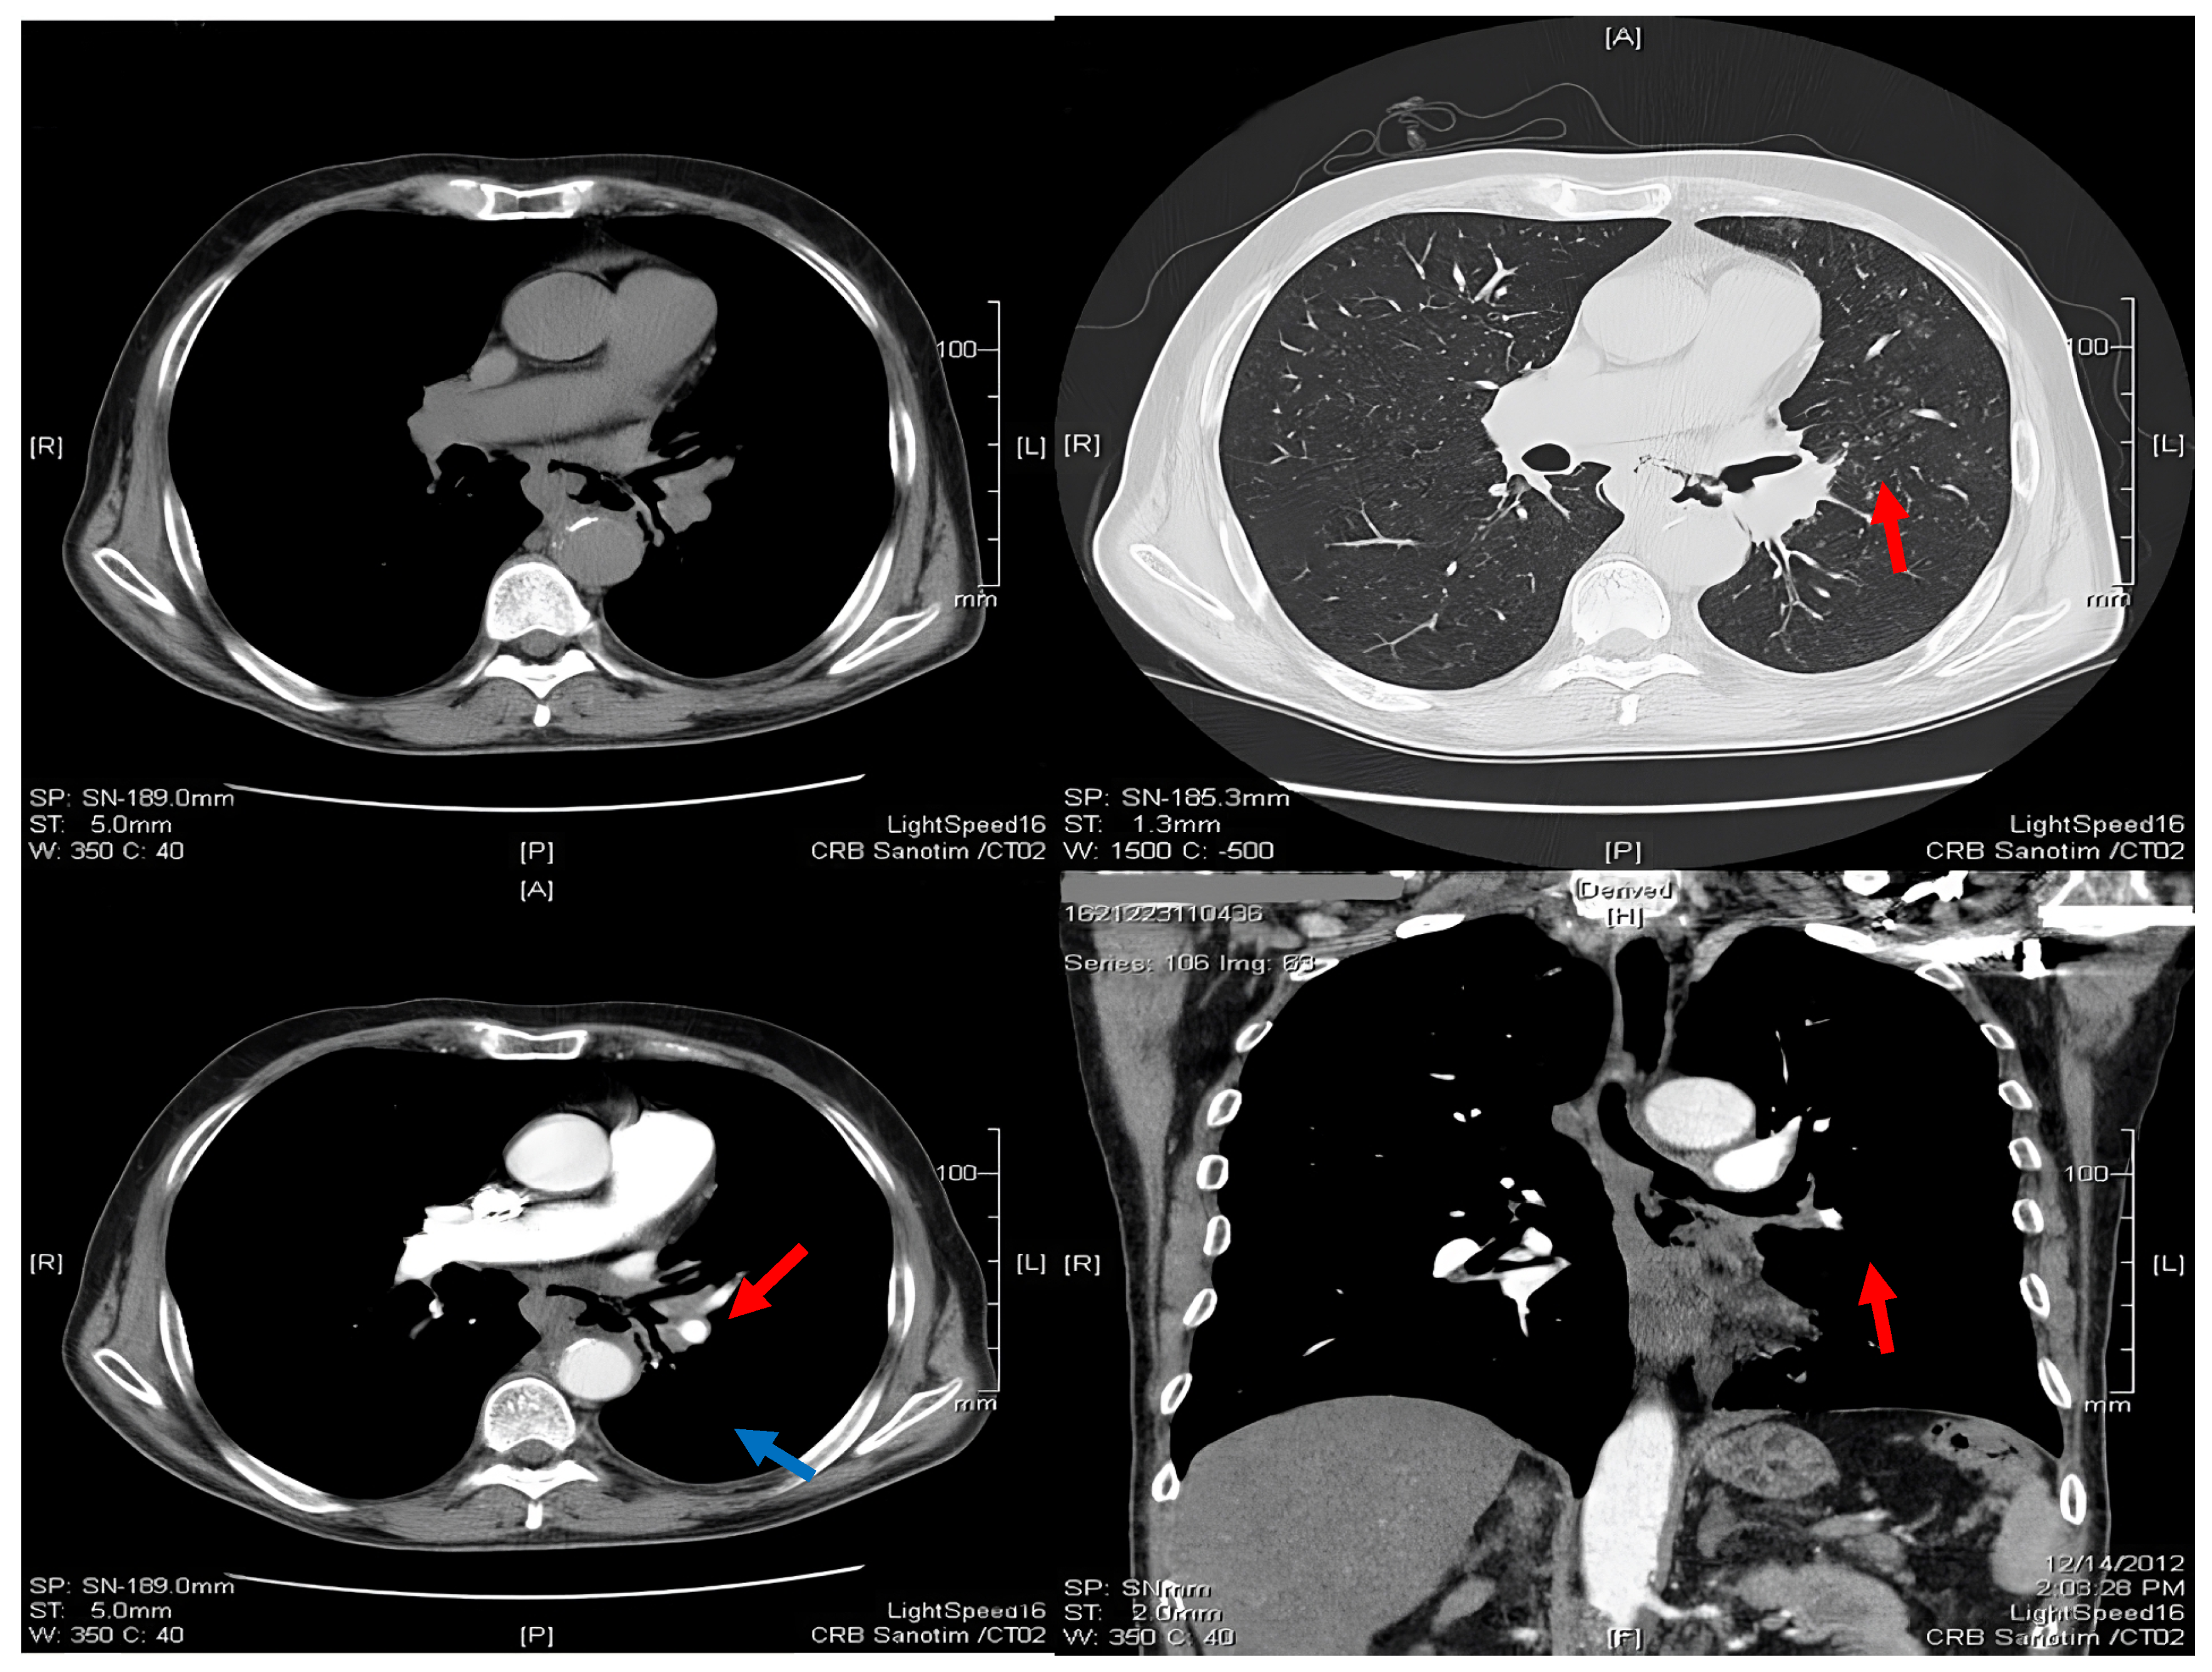

2.1. Thoracic Computed Tomography